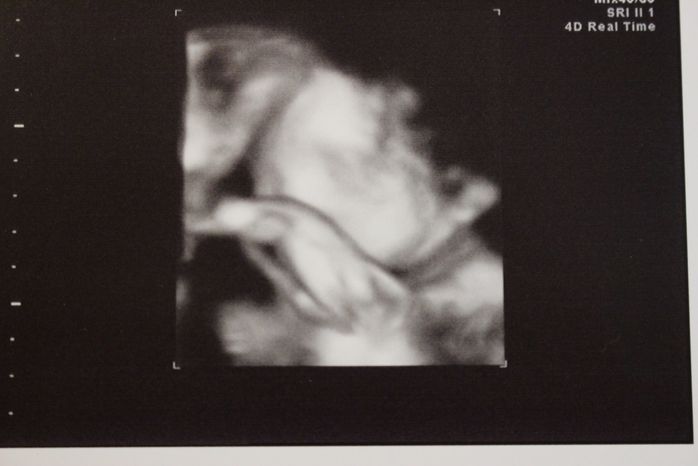

妊娠24週目の4Dエコー写真 (一部)

妊娠24週目4Dの一部画像。手で顔を隠すしぐさと、首にへその緒を巻いている様子が見えます。赤ちゃんの体重727g母体の体重60kg!つわりもおさまった頃で体重管理を意識し始めた時期です。この頃、母親学級で知り合った同じ産院で分娩予定のプレママが管理入院することになり、健診の帰りにお見舞いに行きました。